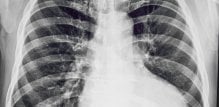

uvećano srce (kardiomegalija) Budite prvi i komentirajte! 1 min čitanja Tomislav Stanić mag. educ. philol. croat. Tekst Dana Za vas izdvajamo Piše psihologinja Ljudi koji stalno kasne: Lijenost ili ozbiljan problem? Marija Šimunić 3 min čitanja Članak objavljen: 30-12-2025 Zatvori Podijelite članak Facebook Twitter Whatsapp Viber Kopirajte adresu